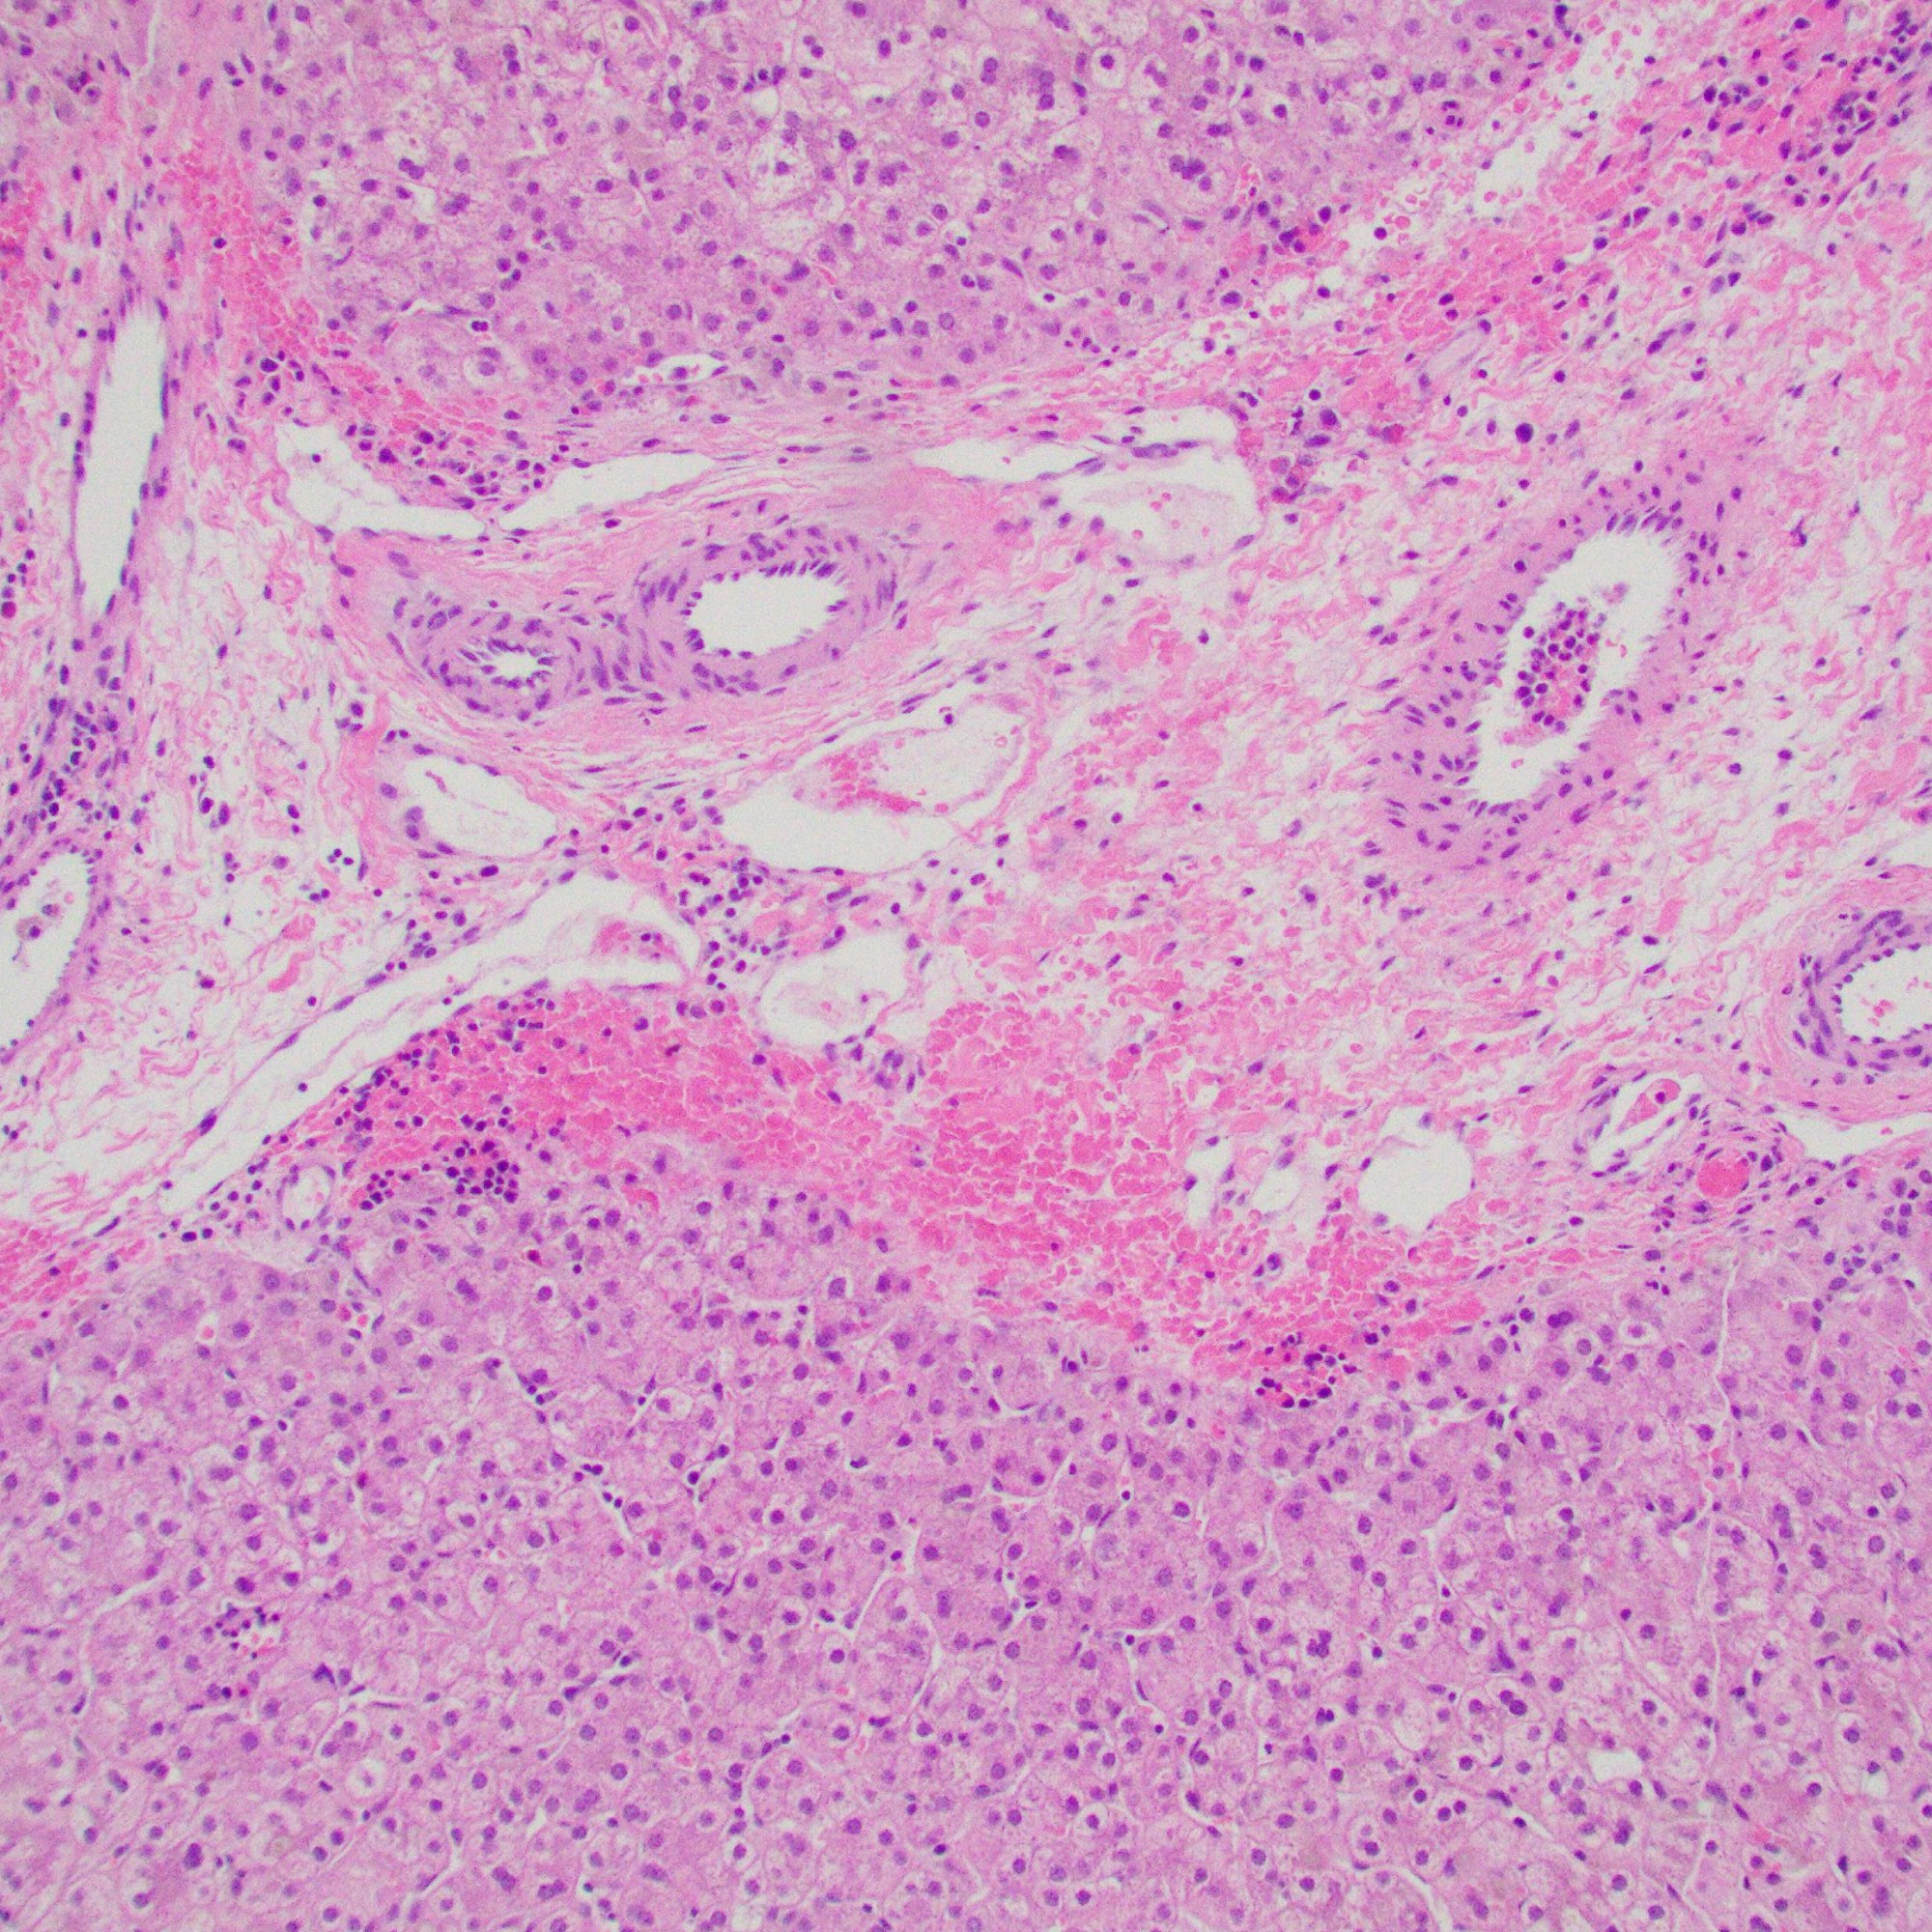

Portal tracts show markedly reduced interlobular bile ducts.

- Histology

- Portal tracts are devoid of bile ducts;

- Ratio of bile ducts to portal tracts: <0.5 (normal: 0.9 to 1.8)

- Ductular proliferation: rare or milder than BA

- Giant cell transformation: can be seen, especially <1y